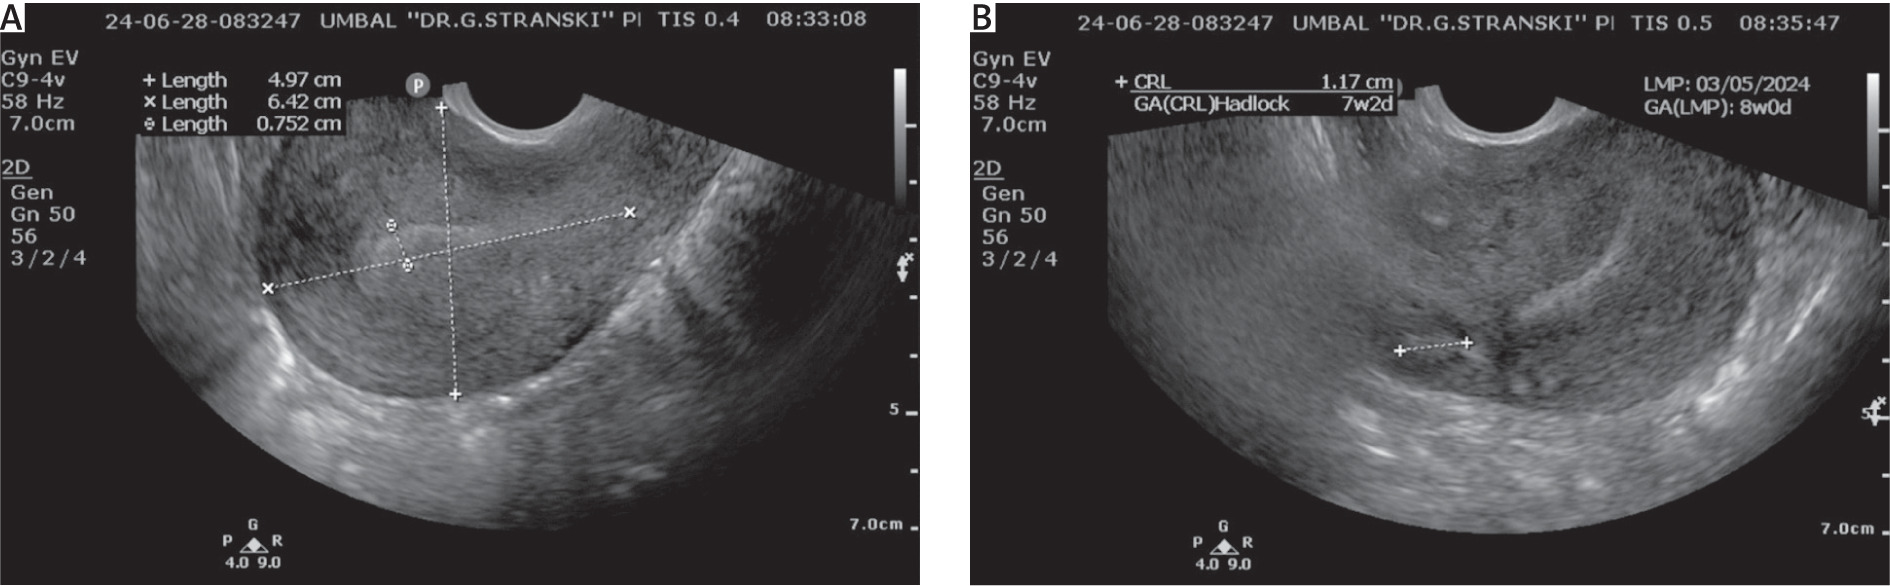

A 38-year-old multiparous woman presented with secondary amenorrhoea, positive pregnancy urinary test, and subjective symptoms of early pregnancy. Her obstetric history included 5 normal vaginal deliveries and 2 spontaneous abortions in early gestational age, and her past surgical history included appendectomy. The patient denied any other comorbidities or medication intake. Vaginal examination established a normal cervix, normal vaginal discharge, anteflexed uterine body that was normal in size and mobility, left adnexa was normal on palpation, there were no pelvic masses, and peritoneal signs were negative. Transvaginal ultrasound revealed an empty uterine cavity and an embryo within the gestational (GS) sac localised in the interstitial part of the right fallopian tube, with no signs of cardiac activity.

The crown-rump length (CRL) of the embryo was 11.7 mm corresponding to 7 + 2 gestational weeks (g.w.).

The diagnosis of IP was hypothesised when the patient presented with amenorrhoea, at an estimated gestational age of 8 g.w. (Fig. 1).

A) Transvaginal ultrasound indicating empty uterine cavity, B) suspected right interstitial pregnancy